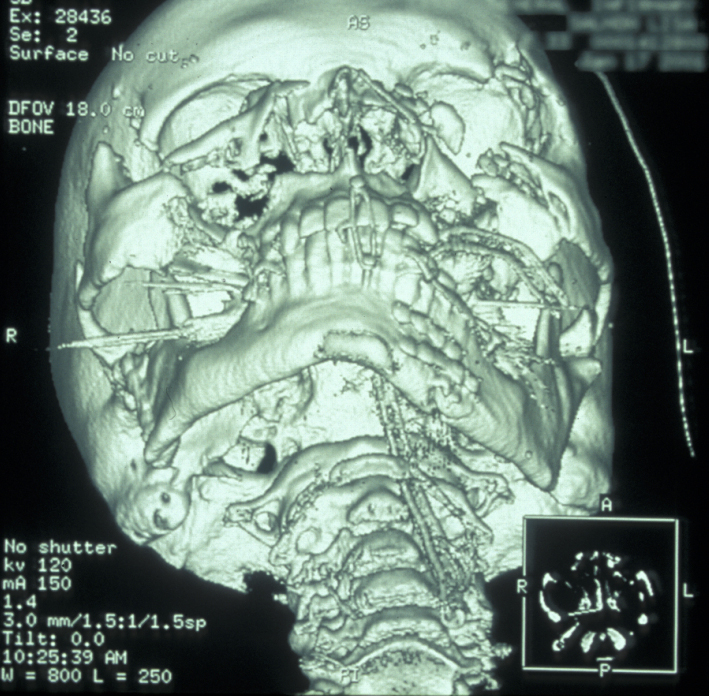

CT scans also allow 3D reformatted images of the facial skeleton to be produced as shown in Figure 12.

Figure 12: Three-dimensional reconstruction of a midface fracture.